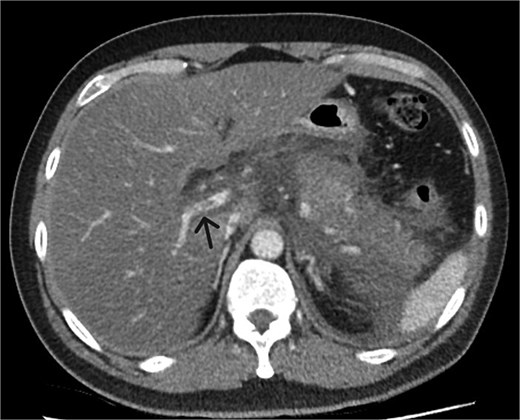

A 39-year-old male presented with one week of worsening epigastric pain radiating to the back, with vomiting, jaundice, and dark urine. His past medical history included depression and alcohol-related liver disease without cirrhosis. On admission he was afebrile, had a soft abdomen with epigastric tenderness worse on palpation, tachycardic, and normotensive. Initial investigations showed a lipase of 2600 U/L, C-reactive protein 238 mg/L, lactate 3.4 mmol/L, and bilirubin 100 μmol/L (Table 1). Abdomen and pelvic computer tomography (CT) demonstrated body and tail pancreatitis, fat stranding, portal vein thrombus, and early necrosis signs, with no choledocholithiasis (Figs 1–3).

Coronal CT image demonstrating body and tail pancreatitis with potential early signs of necrosis.